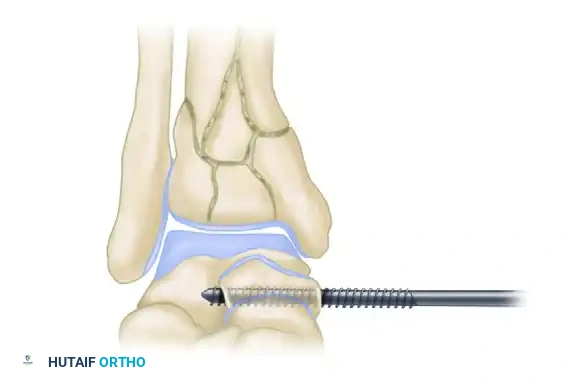

HYBRID EXTERNAL FIXATION

Hybrid external fixation combines the principles of Ilizarov tensioned fine wires in the periarticular (epiphyseal) segment with standard half-pins in the diaphyseal segment. This construct provides robust stability while preserving the soft tissue envelope, making it ideal for spanning complex diaphyseal-metaphyseal fracture extensions.

Biomechanical Considerations

The surgeon must possess a deep understanding of hybrid biomechanics to prevent construct failure.

* Flexibility vs. Stability: In a landmark biomechanical study, Yang et al. demonstrated that a standard bar-ring hybrid fixator (a unilateral fixator body connected to a single distal ring) is excessively flexible, particularly in cantilever bending.

* Construct Optimization: To achieve adequate stability, diagonally placed struts must be added to the unilateral frame. Alternatively, a two-ring hybrid fixator (two distal rings block-connected) provides superior mechanical performance and is the preferred construct for highly comminuted pilon fractures.

* Wire Function: Tensioned fine wires (1.5mm or 1.8mm) act similarly to lag screws. Olive wires can be utilized to compress articular fragments together dynamically.

Indications and Limitations

Hybrid fixators are most appropriate for AO Type A, Type C1, and Type C2 fractures.

* Limitations: In fractures with extreme articular comminution (Type C3), fine wires may fail to achieve adequate purchase. Furthermore, fractures associated with profound tibiotalar instability may not be adequately stabilized by a frame that stops proximal to the ankle joint.

* Intracapsular Risks: Wires placed very distally may enter the ankle capsule. While septic arthritis secondary to pin tract infection is a known risk, clinical experience shows it is significantly less common in the ankle compared to the knee.